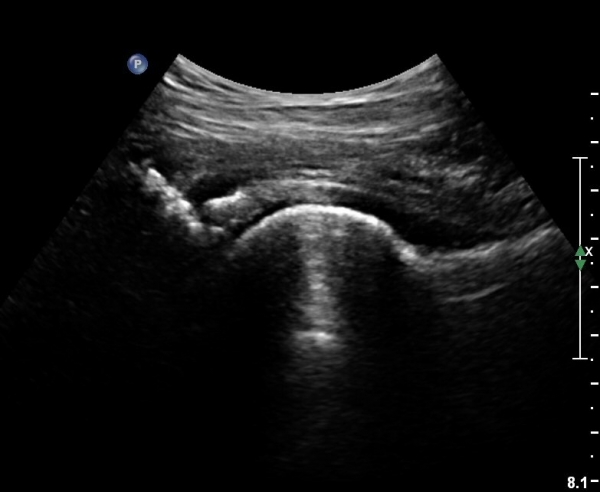

[¾ûµ¢ÀÌ] ¾ûµ¢ÀÌ °üÀý¼ø ÆÄ¿­ÀÇ ÃÊÀ½ÆÄ°Ë»ç(ultrasonography of labrum tear of hip joint)

Sonography of the Acetabular Labrum Visualization of Labral Injuries During Intra-Articular Injections

Sonographic evaluation of anterosuperior hip labral tears with magnetic resonance arthrographic and surgical correlation.